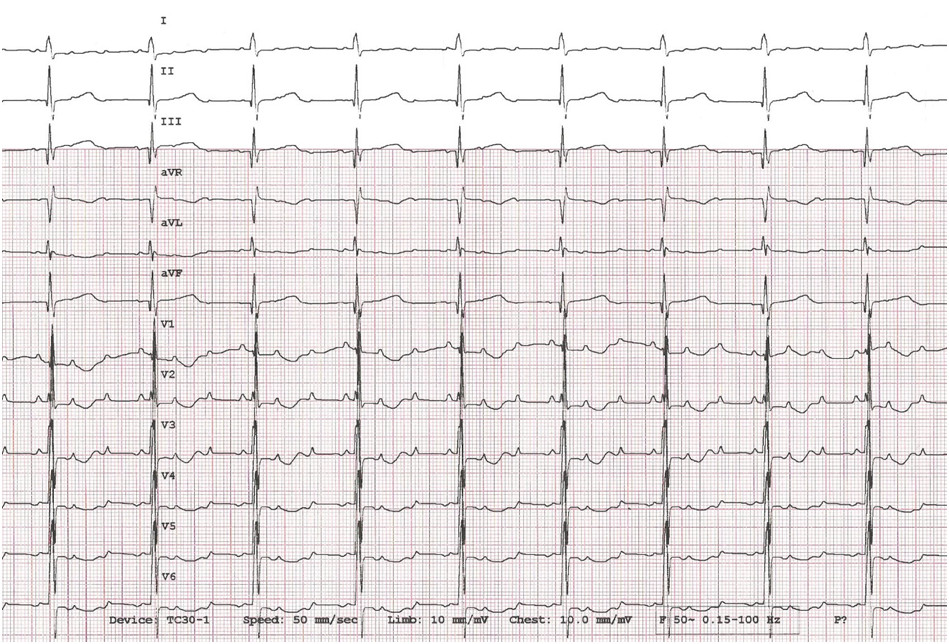

Wskaż prawdziwe stwierdzenie dotyczące zapisu EKG 10 letniego chłopca:

Zapis EKG 11-letniego chłopca to:

1) stymulacja dwujamowa DDD;

2) stymulacja jednojamowa z prawej komory VVIR;

3) stymulacja jednojamowa przedsionka AAI;

4) zespoły QRS wykazują cechy bloku prawej odnogi pęczka Hisa;

5) zespoły QRS wykazują cechy bloku lewej odnogi pęczka Hisa.

Prawidłowa odpowiedź to: